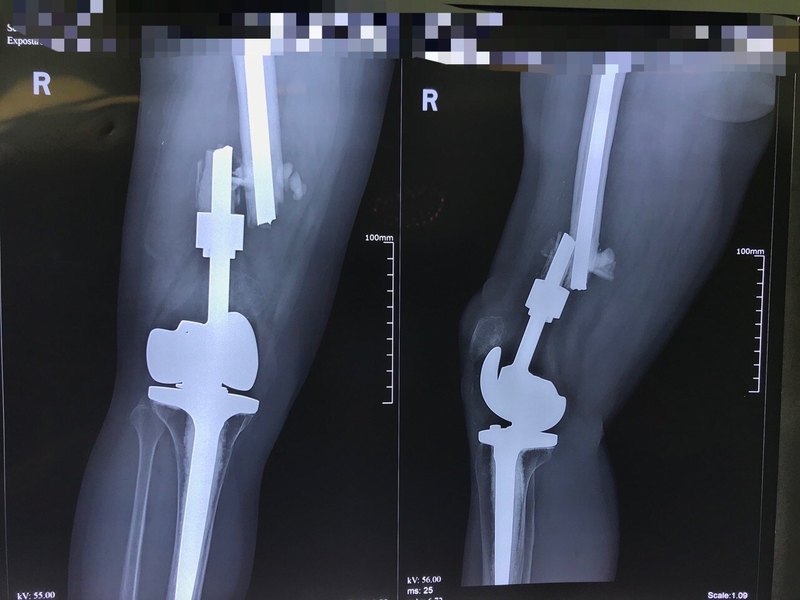

這是一位可愛的老太,其68歲。15年前檢查得知膝關(guān)節(jié)腫瘤,行全膝關(guān)節(jié)置換術(shù)后,手術(shù)非常順利、術(shù)后恢復很好。 由于老人家家里沒有什么事做,加上術(shù)后恢復良好,愛上了廣場舞,經(jīng)常跳跳廣場舞,長期的廣場舞跳下來,導致假體金屬疲勞而斷裂,不得不辛苦的從外地來到我院再次行翻修手術(shù)治療,手術(shù) 假體嵌入水泥牢固無法取出,最后不得不行全股骨置換手術(shù),術(shù)后恢復的相當良好。 愿健康平安幸福享晚年生活,適度鍛煉即可。